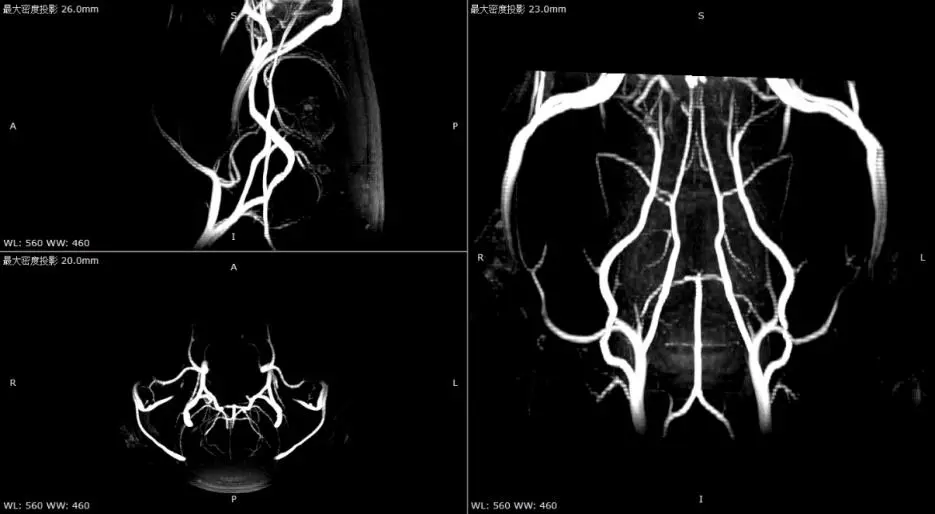

TOF-3D序列成像对高流速血管(如动脉)显示清晰,对低速血管(静脉、微小血管)敏感性差。

T2WI清晰显示灰质(稍高)、白质(稍低)、脑脊液(高信号);3D-TOF可清晰显示脑动脉。